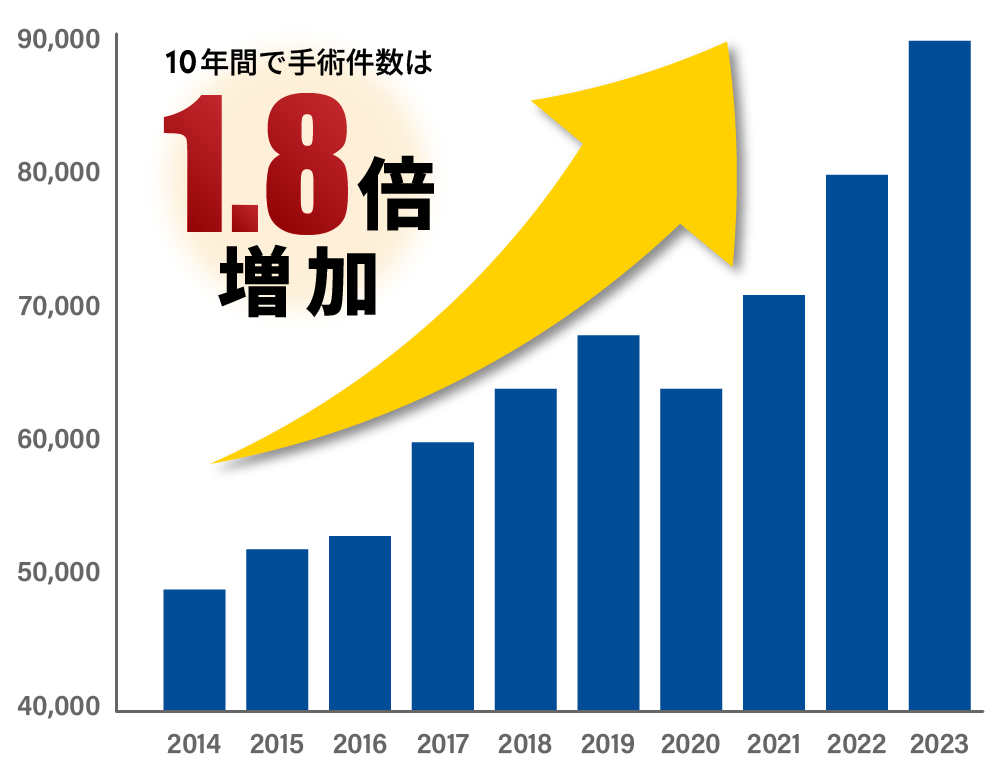

手術件数は年々増加しています

日本では、2014年からの10年間で人工股関節全置換術(THA)の件数が年間4万件以上増加しました。高齢者や女性を中心に、年々多くの方がこの手術を選択しています。

- 人工股関節全置換術の認知度の向上

- 手術技術・人工関節素材の進歩

- 高齢化の進展

これらの理由により、人工股関節置換術は今や社会的にも一般的な治療法として定着しています。